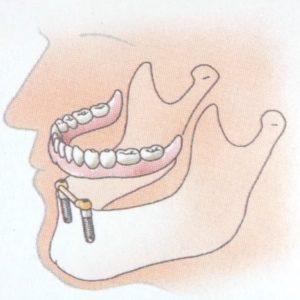

- Bij het ontbreken van één tand of kies, wordt een implantaat ter plaatse van het ontbrekende gebitselement in de kaak geplaatst en wordt daarop een kroon van keramiek of een combinatie van keramiek met metaal vastgezet..

- Bij het ontbreken van enkele tanden of kiezen plaatst men twee of meer implantaten en maakt men een vastzittende brug. Deze brug vervangt de ontbrekende tanden en/of kiezen.

- Bij het ontbreken van alle tanden en kiezen.

- worden twee of meer implantaten geplaatst. Daarop worden knopjes of staafjes gemaakt waarop een overkappingsprothese vastklikt. Deze is uitneembaar, maar zit wel veel vaster dan een normale gebitsprothese. Soms wordt er een niet-uitneembare brug op vervaardigd, maar dan heb je wel tenminste vier implantaten nodig en is de behandeling veel duurder omdat de verzekeraar een dergelijke behandeling in het algemeen niet vergoedt.